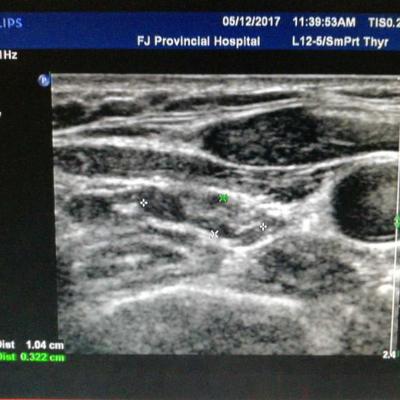

男性,40岁,70 Kg,175 cm, 风华正茂,事业正当时,并不嗜酒,却每日应酬不断,新近查肝功能异常,如下图1: 常规排除各种病毒性肝炎,自身免疫性肝炎,药物性肝病等可能,B超提示有脂肪肝,为进一步确定肝损伤程度,肝穿刺病理所见,肝小叶广泛肝细胞脂肪样变,大于50%,气球样变性,中性粒细胞浸润,窦周纤维化。为典型酒精性肝病。中度肝纤维化(S2)。 全球酒精性肝病患病率呈现持续增长趋势。我国尚缺乏酒精性肝病的全国性大规模流行病学调查资料,但地区性流行病学调查显示,我国饮酒人群数量和酒精性肝病的患病率有迅速上升趋势。华北地区流行病学调查显示,从上世纪80年代初到90年代初,嗜酒者在一般人群中的比例从0.21%升至14.3%;本世纪初,南方及中西部省份流行病学调查显示,饮酒人群增至30.9%~43.4%。 酒精性肝病占同期肝病住院患者的比例也在不断上升,从1991年的4.2%增至1996年的21.3%;来自解放军第三0二医院的研究报道,2002年至2013年十余年间,因酒精性肝病住院的患者比例上升了170%。由此可见,在我国,酒精所致的肝脏损害已经成为一个不可忽视的问题。 酒精滥用和依赖显著增加了酒精性肝硬化的发生风险,其中在40~59岁人群最为显著。此前曾有报道,长期的每天饮酒,尤其是饮白酒或啤酒,更易引起酒精性肝硬化。 一份回顾性研究结果显示,早期/代偿期酒精性肝病患者的5年肝病相关死亡率为13%,而失代偿期患者则高达43%;早期/代偿期酒精性肝病患者的长期预后受到肝纤维化分期的影响,其中严重纤维化(F3/4)对10年死亡率有重大影响;对于失代偿期酒精性肝病患者,临床特征(性别:女性)、肝衰竭的生物化学指标(胆红素、国际标准化比值)、组织学特征可以预测患者的长期生存率;随访期间,无论代偿期还是失代偿期酒精性肝病患者,戒酒都是生存率的重要预测指标。 也有研究报道,胆红素淤积的出现及其程度、巨型线粒体缺失、多形核白细胞浸润程度与酒精性肝炎患者的死亡率显著相关;酒精性肝炎组织学评分对于预测糖皮质激素的疗效和死亡率具有很高的准确性。 酒精性肝病相关恶性肿瘤不容忽视。来自日本的一项多中心研究结果显示,和非酒精性脂肪肝相比,酒精性肝病导致的肝癌的患者更年轻,肝纤维化水平更高,芬兰的一项包括1873例酒精性肝病患者的调查结果显示,酒精性肝病患者的恶性肿瘤发生率显著高于对照人群;其中重症酒精性肝病患者的肝细胞肝癌、上消化道癌症、胰腺癌等恶性肿瘤发病风险显著升高;该研究还指出,所调查的酒精性肝病患者当中,未发现任何一种恶性肿瘤的发病风险是降低的。